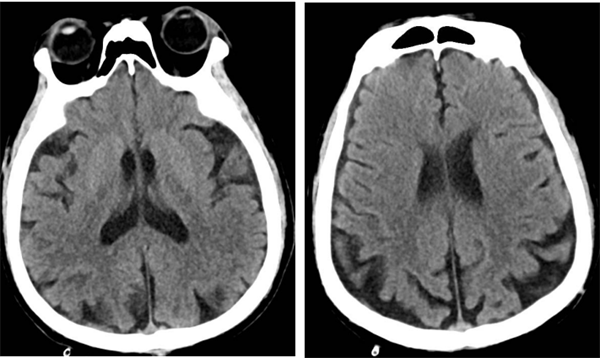

近日,皇冠足球投注网 神经外科收治了一名74岁高龄且伴有多年高血压、糖尿病史的高危患者何先生(化名)。何先生此前已接受过右侧椎动脉、左侧锁骨下动脉支架植入术,但近期因头晕、左侧肢体乏力等症状再次入院。经过详细检查,医生发现何先生右侧颈内动脉起始部存在重度狭窄,狭窄率高达75%,情况危急。

▲术前脑血管造影

术后,何先生顺利苏醒,回到神经外科病房进行监护治疗,术后7天伤口愈合良好拆线出院。8月何先生来皇冠足球投注网 复查,DSA检查提示右侧颈动脉狭窄已完全恢复并无再狭窄,头晕及左侧肢体乏力症状也完全缓解了。

▲术后狭窄完全解除